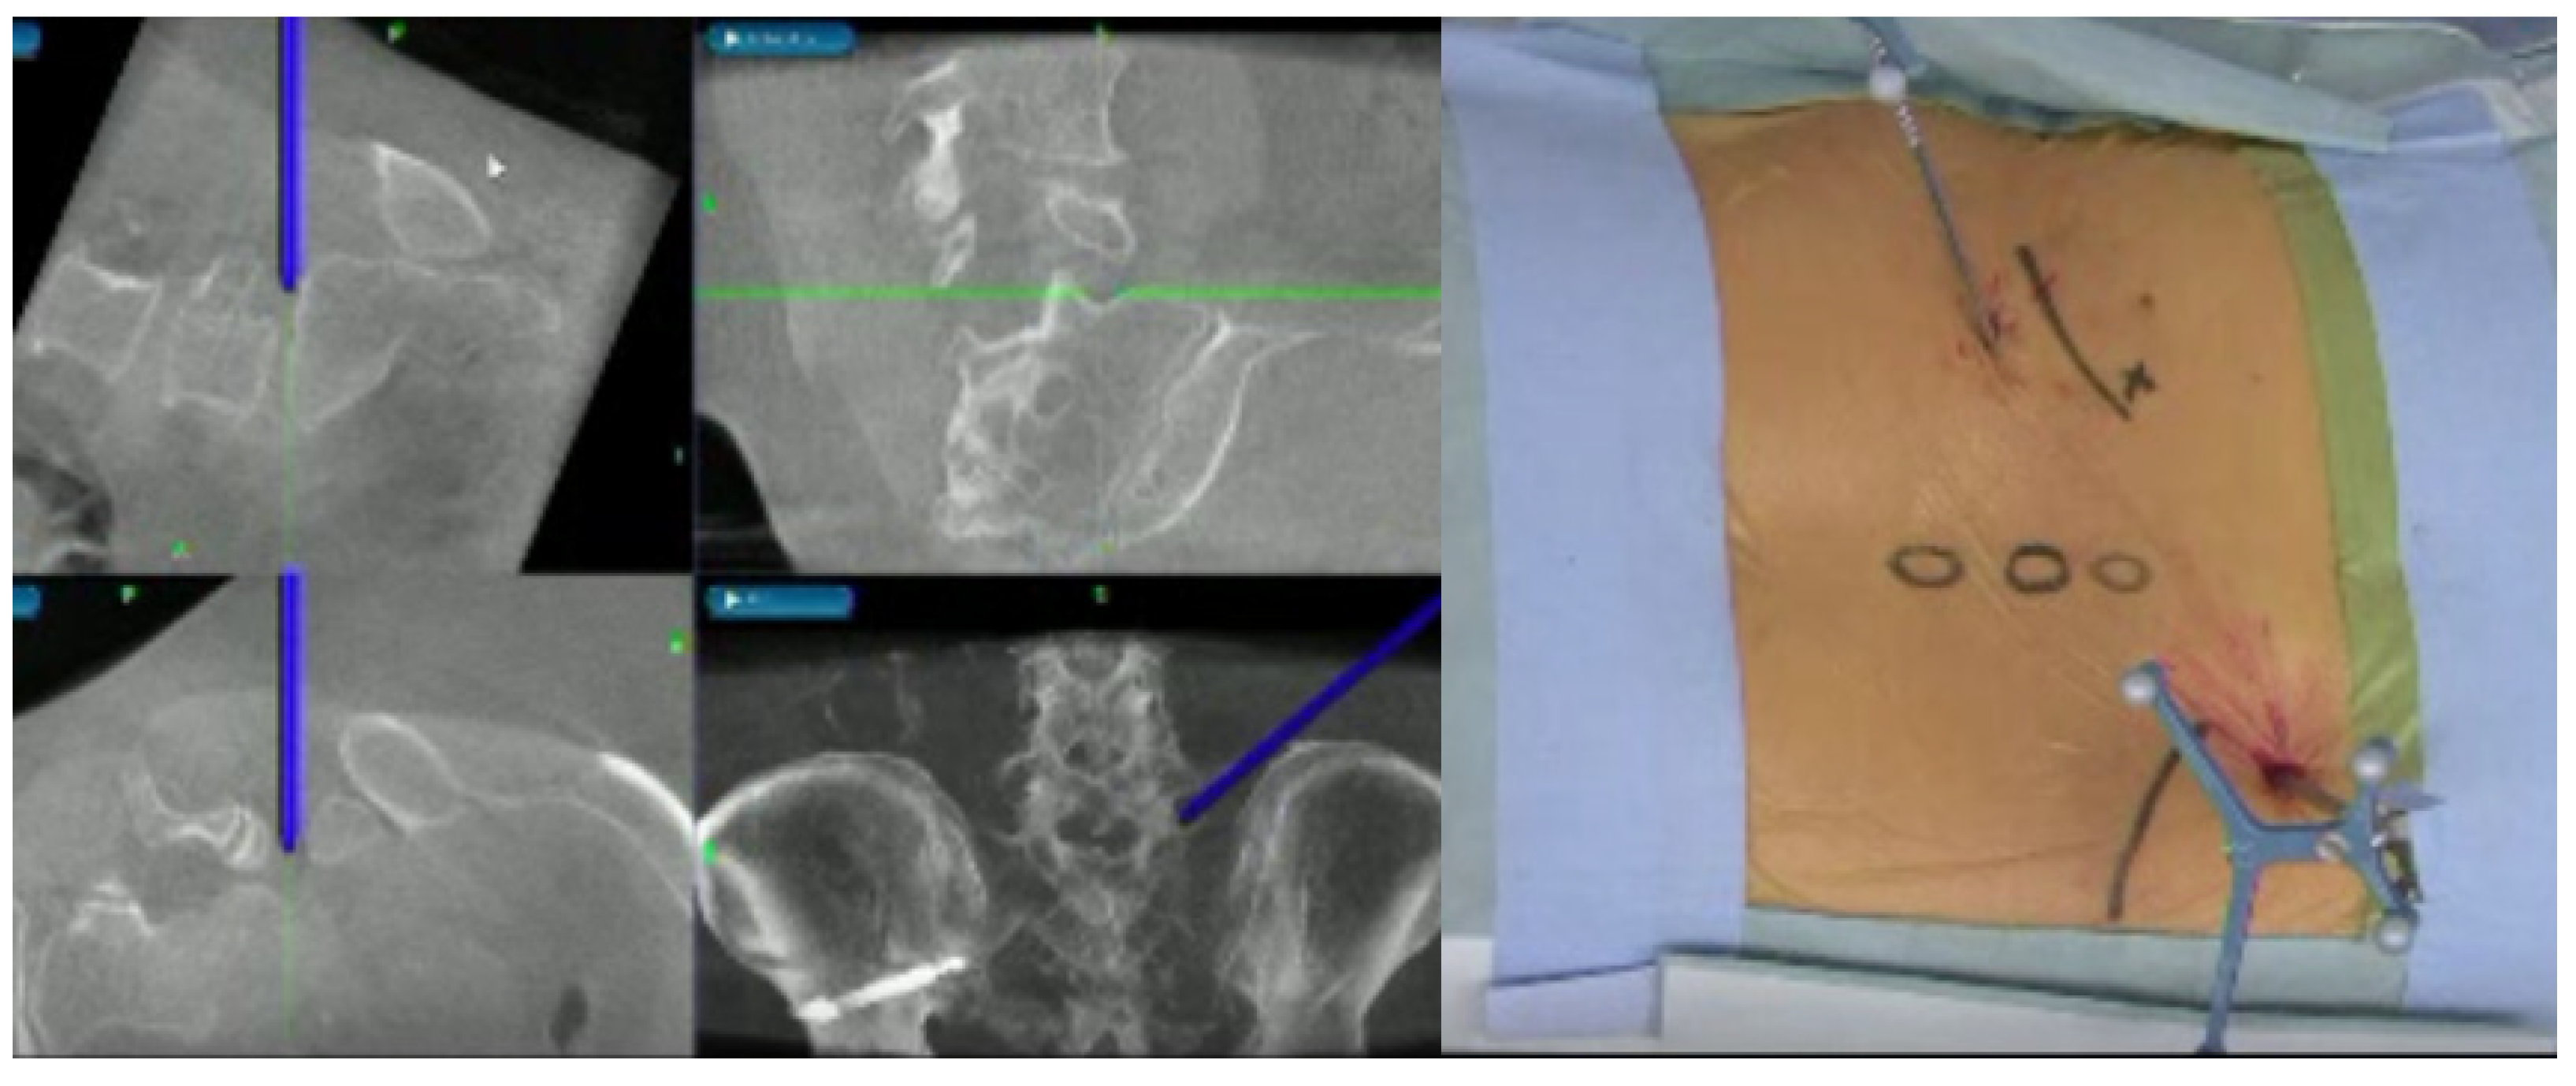

Figure 1.

A 57-year-old female. Right L5-S1 lumbar disc herniation. Fully endoscopic discectomy.

The fusion image combining 3D disc and nerve tissue image with the bony structure was obtained using Synapse Vincent version 6.4 software (Fujifilm, Tokyo, Japan). The first step was justification of the CT image (soft tissue mode) and MR image (FIESTA) in a 2D image using high signals from CSF and disc. The second step was obtaining the 3D bony image from CT, setting the transparency rate of the ilium bilaterally at 0.2 to make the image of the L1 to S2 level. With MRI, images of the neural tissue and disc were made manually. The final step was merging of the bony image from CT and the soft tissue image from MRI. The total time to create the CT/MRI fusion was approximately 5 min (Figure 2).

Figure 2.

MRI and CT medical image fusion.